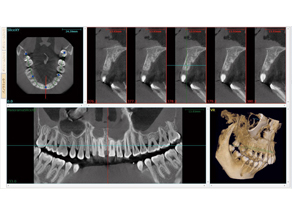

コーンビームCT

歯科用CTとは、歯科に特化したCT装置。エックス線の出し方にコーンビーム方式を用いているため、コーンビームCT(CBCT)とも言います。主にインプラント、顎の骨の中に埋まっている親知らずの抜歯、矯正歯科症例での顎骨や歯の傾きの状態、などの歯科治療・診断に大変有効です。三次元の高画質画像を用いることで、断層方式パノラマエックス線撮影法や口内法エックス線撮影法では判別できない、痛みや症状の原因の解析にも役立ちます。当院では大学病院や総合病院に行く事なく鮮明な画像が得られます。